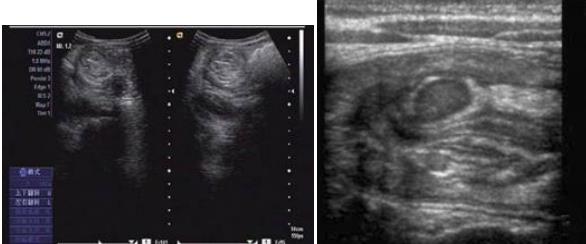

圖示:該患兒當(dāng)時(shí)聲像圖表現(xiàn)

超聲圖像表現(xiàn)

1、腸套疊部位顯示邊界清楚的包塊。其橫斷面呈大環(huán)套小環(huán)的特征性表現(xiàn),即“同心圓征”或“靶環(huán)征”。外圓呈均勻的低回聲環(huán)帶,系鞘部腸壁回聲,低回聲帶系水腫增厚的反折壁及其與鞘部之間的少量腸內(nèi)液體形成。在大的外圓內(nèi),又有一個(gè)小低回聲環(huán)帶,形成內(nèi)圓。內(nèi)、外圓間為高回聲環(huán),中心部為高回聲團(tuán),其邊緣欠光整。套疊部的縱斷面呈“套筒征”或“假腎征”。有時(shí)可能顯示套疊的頂部和頸部,頂部呈指頭狀盲端。“假腎征”通常是在套疊時(shí)間較長(zhǎng),腸壁發(fā)生嚴(yán)重水腫時(shí)出現(xiàn),或是成人患者存在腸管腫瘤或息肉時(shí)出現(xiàn)。